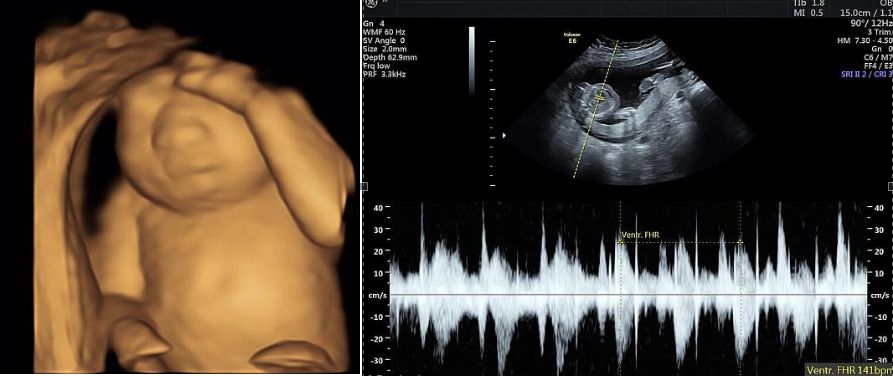

Badania dziecka Keri i Royca Young

Badania dziecka Keri i Royca Young © Facebook